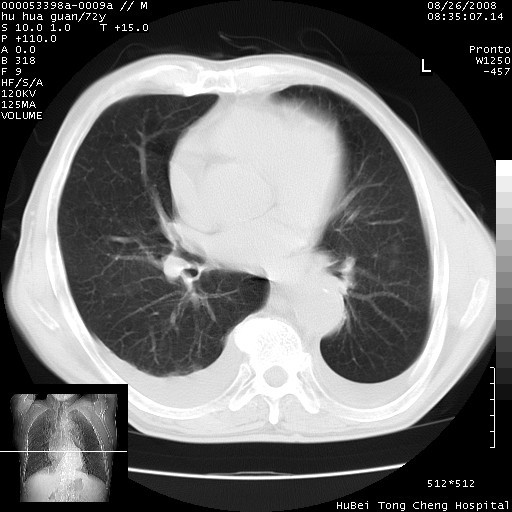

标题: CT15582:M,72Y。请老师帮分析胸部病变。

考虑胸主动脉下段夹层破裂。

考慮夾層動脈瘤破裂可能,建議增強掃描。

可以明确的说。肯定不是主动脉夹层破裂出血!考虑为淋巴瘤或间叶组织来源的恶性肿瘤可能性大。右肺小结节建议薄层观察,如能发现恶性征象,那椎前改变就考虑为转移所致。至于双侧少量胸水乃静脉血回流受阻所致。

图像及窗宽窗位均不理想。周围性肺癌/胸腔积液/纵隔积液。

1、右肺周围性肺癌、胸腔积液(双)

2、建议食道吞钡和增强检查排除食道和主动脉病变

3、后纵隔淋巴类肿瘤

1、右上肺结节病变,肺泡癌不除外,请随诊;左下肺近后纵隔病变,考虑纵隔型肺癌侵犯大血管可能;

2、右下肺背段少许炎症,双侧胸腔积液,右下肺纤维索条。

降主动脉前移位,后纵隔占位

后纵隔占位,降主动脉前移位;双侧胸腔积液;应排外食管病变侵犯血管可能;

主动脉瘤破裂

建议排除结核引起的冷脓肿。